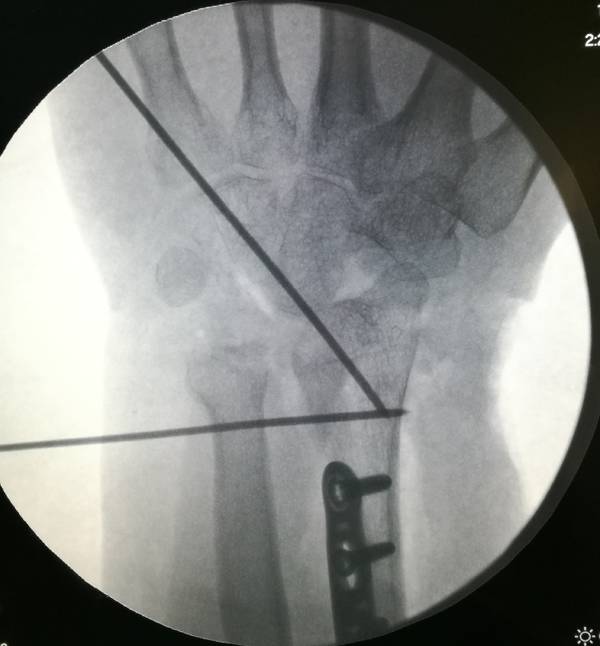

本帖最后由 zhangwenlong 于 2019-1-14 22:04 编辑

桡骨远端骨折术中透视

侧位,前臂远端抬高20度拍摄关节面切线位正位,后前位,前臂抬高13度拍摄关节面切线位

前臂树立,屈腕拍摄桡骨远端背侧切线位片

可以更好的判断螺钉长短